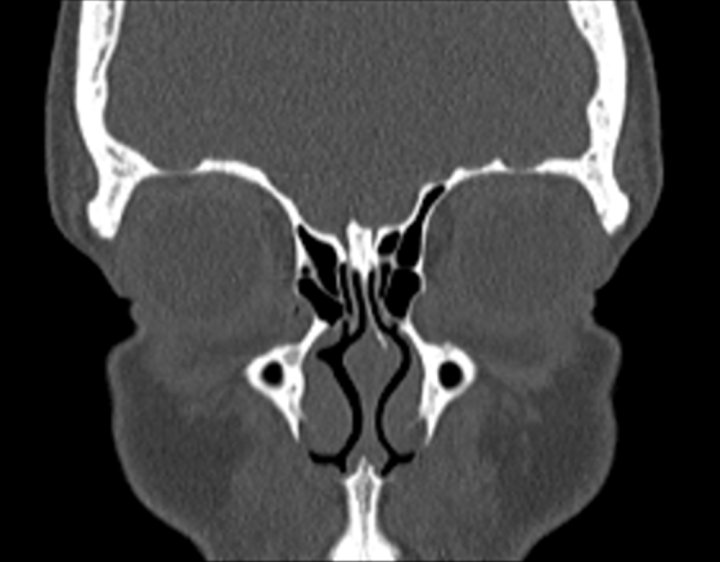

Click any image for labels.